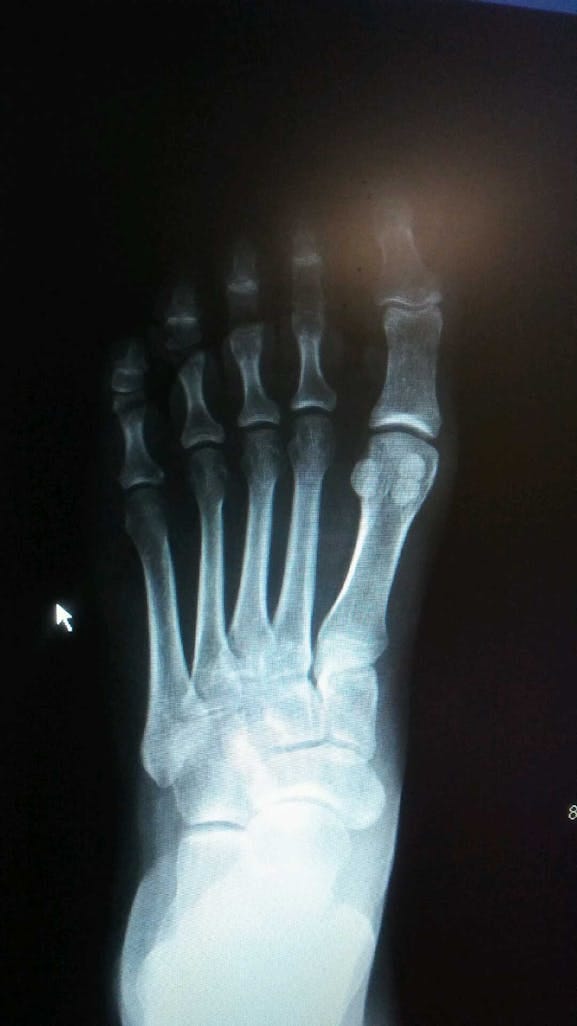

So, what about that xray of the patient’s foot? Well, it belongs to the patient, no doubt. Your data should be your data. But the problem is that it’s not, right? Large medical group and insurance companies are using it without your expressed permission.

When I take your foot x-ray and post it to get clinical feedback, that’s considered disclosing protected health information. Even if the intention is good, I need direct patient consent.

This makes the work much harder. Because now I am exposed to risk and have to find my patient and not only get their permission but I have to get permission from my medical group to use the image which was taken on their premises.